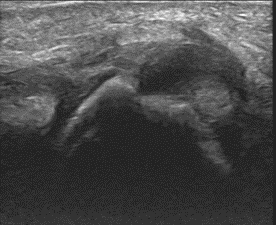

Long axis ultrasound of the thumb at the level of the metacarpophalangeal joint.

The white arrows demonstrate the adductor pollicis aponeurosis. The blue trace outlines the torn and retracted ULC from the base of the proximal phalanx. It has flipped proximally – lying superficial to the aponeurosis.